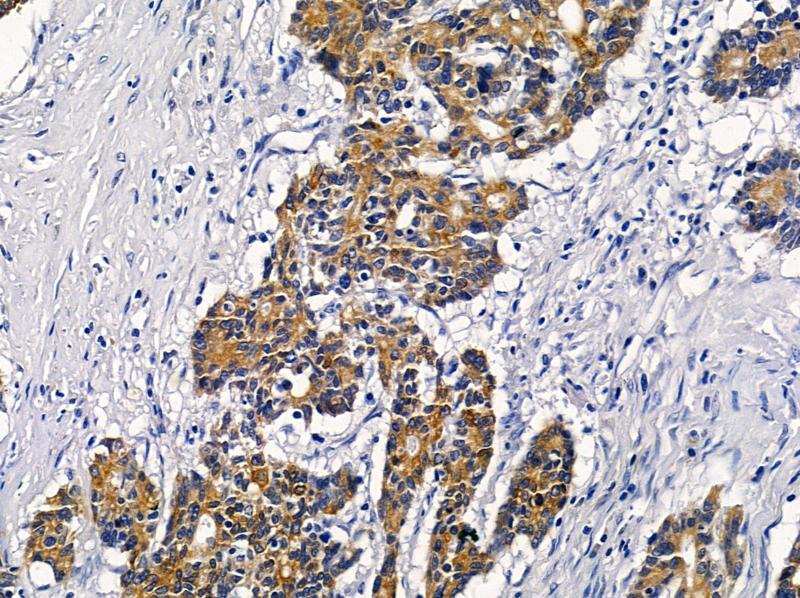

Supportive validation

- Submitted by

- Invitrogen Antibodies (provider)

- Main image

- Experimental details

- Immunohistochemistry analysis of VN1R2 in human colorectal cancer. The sample was formaldehyde fixed and a heat mediated antigen retrieval step in citrate buffer was performed. Samples were incubated with VN1R2 polyclonal antibody (Product # PA5-102261) using a dilution of 1:100 (4°C overnight) followed by HRP conjugated anti-Rabbit secondary antibody.